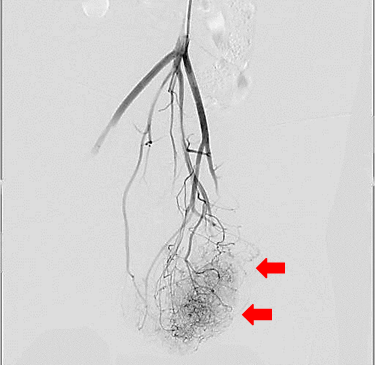

【実施症例】腰下リンパ節に転移した血管肉腫に対する動注療法

ゴールデン・レトリーバー、11歳、雄。

腰下リンパ節に転移した血管肉腫。

腫瘍の頭側の腹大動脈にリザーバーを設置し、抗がん剤の投与を行った。腫瘍は1/3以下に縮小が認められた。

血管肉腫が転移した腰下リンパ節

腫瘍陰影(DSA画像)